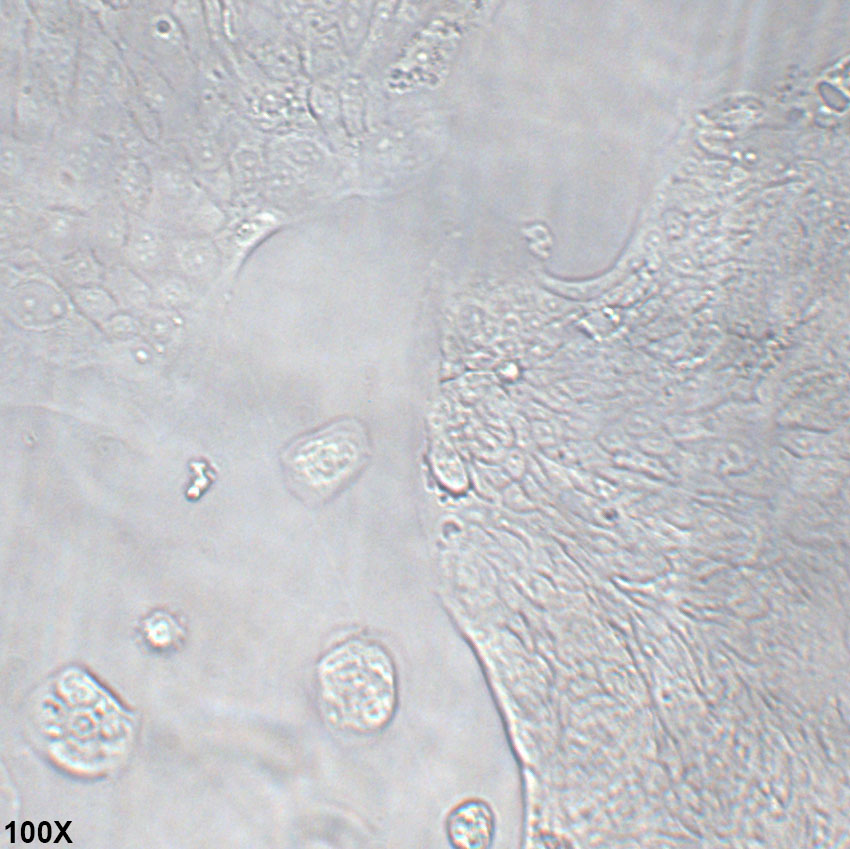

形态特征 上皮细胞样

生长特征 贴壁